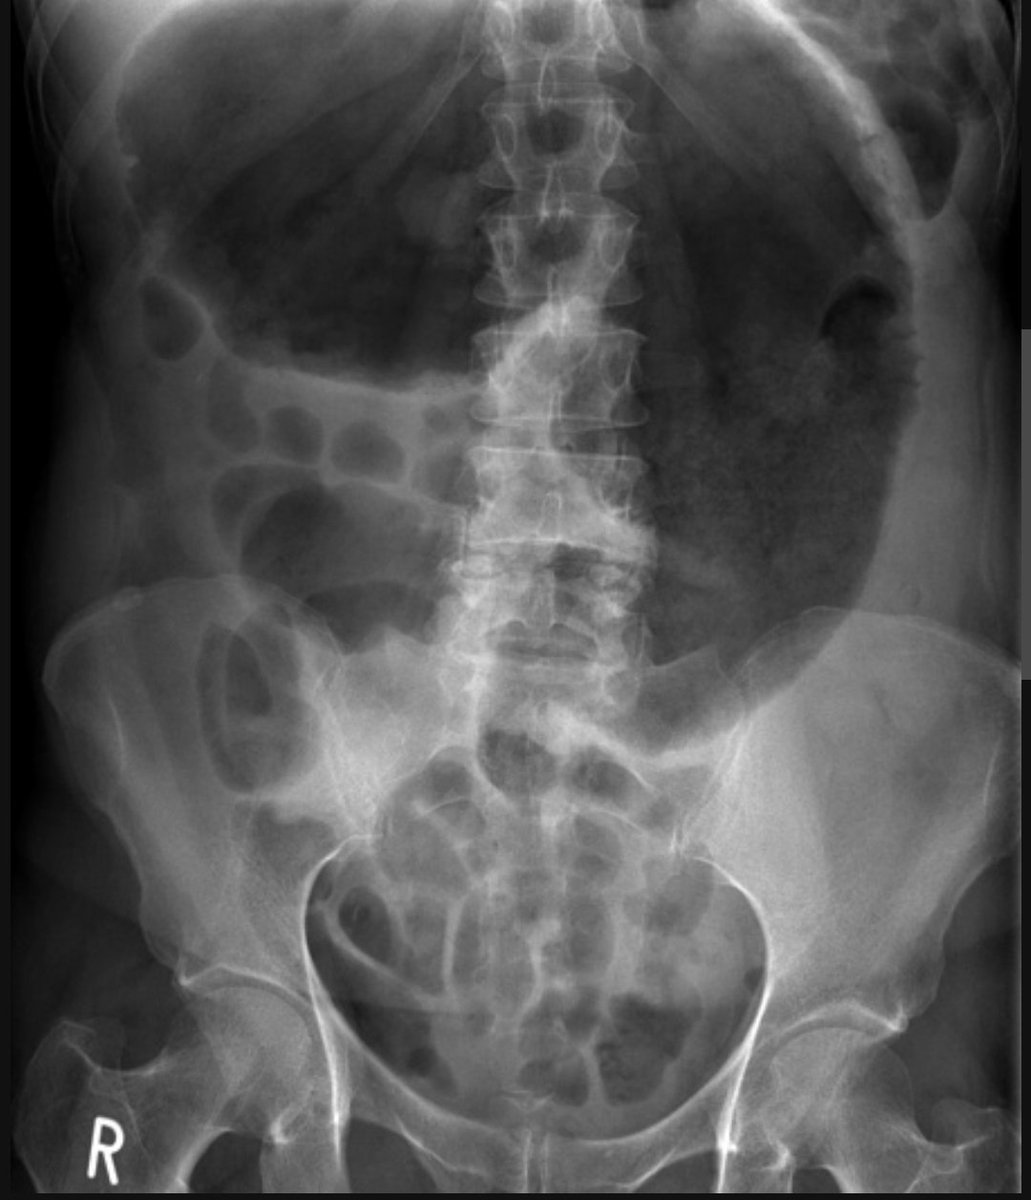

Abdominal pain, abdominal distension and vomiting.

What is this sign? Image

Caecal volvulus - 'Caecal embryo' sign

The caecum is grossly dilated and is not located in the RIF which is occupied by small bowel. Image

Caecal volvulus

👉 the dilated caecum takes on a shape similar to a mammalian embryo.

That is, the formation of a large dilated caecal pole (head), with one or two further 'segments' (body and tail)